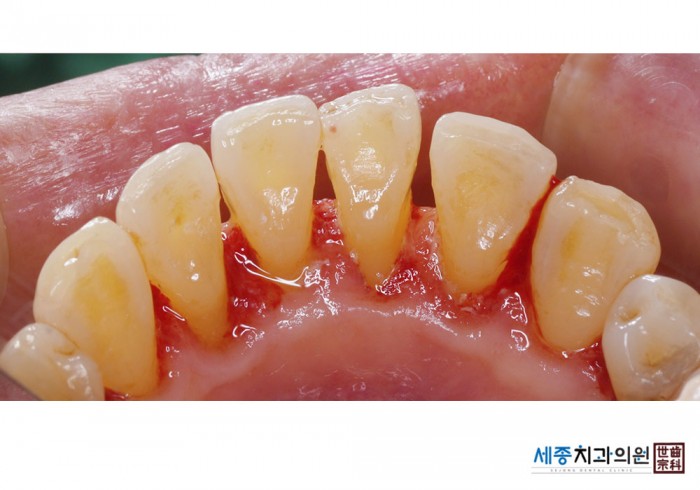

[스케일링] 치주질환 예방 스케일링

치료전 : 2025-09-23

치료후 : 2025-09-23

가글마취&저주파 스켈러를 사용한 착색제거 스케일링